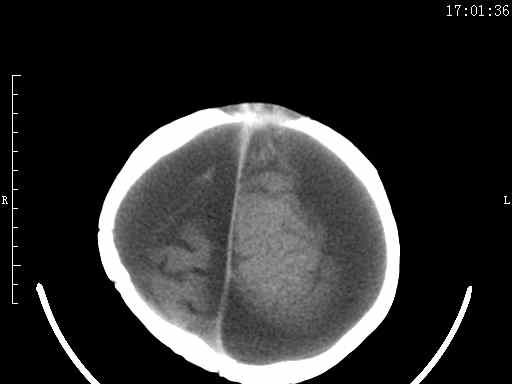

以下是引用余辉在2009-5-30 17:43:00的发言:[br]外围性脑积水在蛛网膜下腔,这个不像,双侧客部液区增宽,内见对称性弧形线状高密度影,边缘清晰锐利,右侧后端终止于冠状缝,左侧终止于人字缝,应该是硬脑膜.双侧硬膜下液区增宽,脑皮质受压变平,脑沟裂无显著增宽,考虑1双侧额颞顶部慢性硬膜外血肿伴硬膜下积液或慢性血肿2双侧慢性硬膜下积液伴硬脑膜剥离并有交通积液(反正考虑硬膜下及硬膜外的慢性血肿或积液)